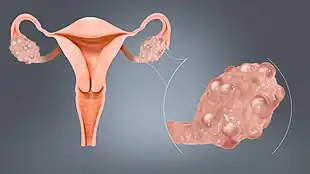

| A simple ovarian cyst of most likely follicular origin | |

An ovarian cyst is a fluid-filled sac within the ovary.[1] Often they cause no symptoms.[1] Occasionally they may produce bloating, lower abdominal pain, or lower back pain.[1] The majority of cysts are harmless.[1] If the cyst either breaks open or causes twisting of the ovary, it may cause severe pain.[1] This may result in vomiting or feeling faint,[1] and even cause head aches.

Most ovarian cysts are related to ovulation, being either follicular cysts or corpus luteum cysts.[1] Other types include cysts due to endometriosis, dermoid cysts, and cystadenomas.[1] Many small cysts occur in both ovaries in polycystic ovary syndrome (PCOS).[1] Pelvic inflammatory disease may also result in cysts.[1] Rarely, cysts may be a form of ovarian cancer.[1] Diagnosis is undertaken by pelvic examination with an ultrasound or other testing used to gather further details.[1]